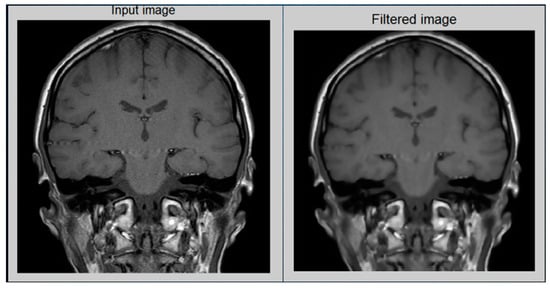

In the preprocessing step, image enhancement is used as the first step. In this study, a contrast stretching filter was used for the enhancement of an MRI image for this greyscale image, since it functions relatively better. Without distorting the relative grey level intensities, the contrast stretching filters improved the contrast of an image [12]. As a consequence, an enhanced image does not offer an unnatural look like the equalization of histograms. Via contrast stretching, the image contrast is enhanced by stretching the spectrum of contrast values to spam the target scale from 0’s to 1’s. The uncertainty which can occur in the regions of images has been removed by contrast stretching enhancement. For this analysis, Figure 5 demonstrates the performance of a contrast-stretching-based enhancement test image.

Figure 5.

MRI image after preprocessing: (Left) Original image and (Right) Enhanced image.